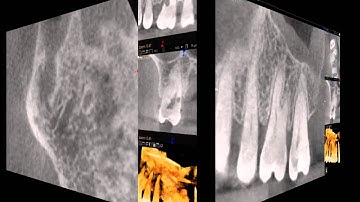

CBCT scan diagnoses resorption defect in upper first molar